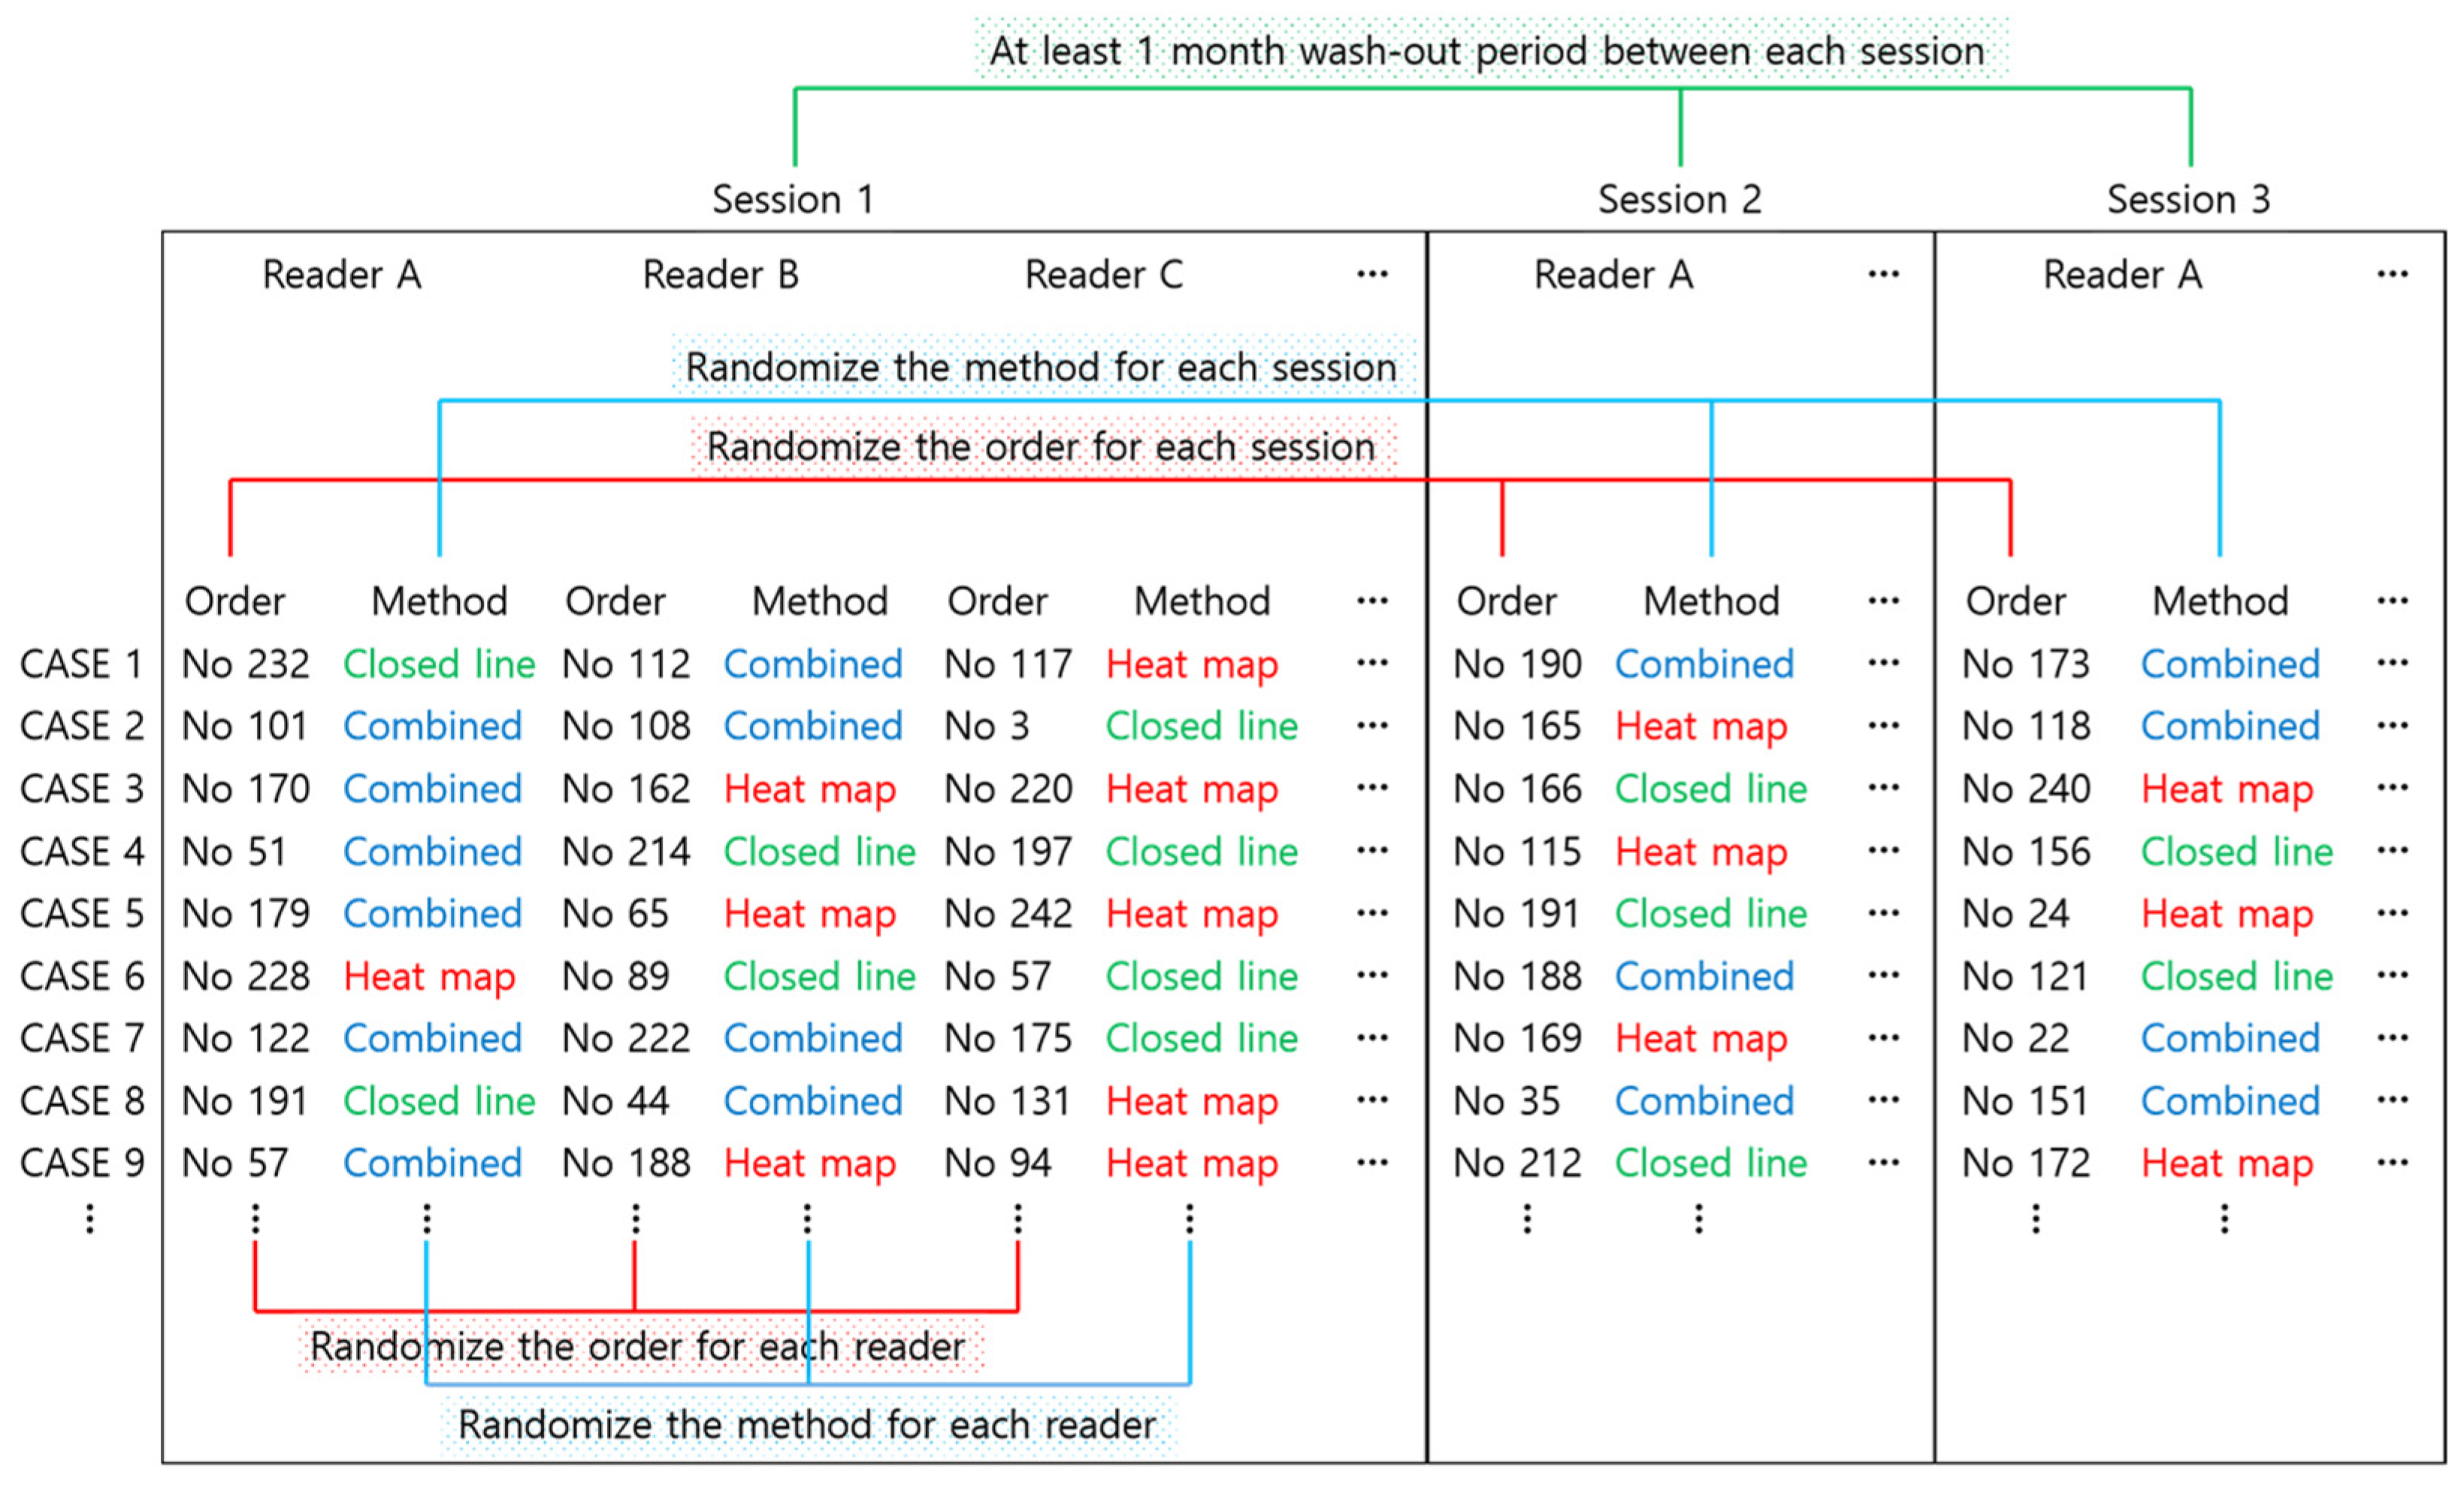

2.3. AI-CAD

2.4. Reader Test